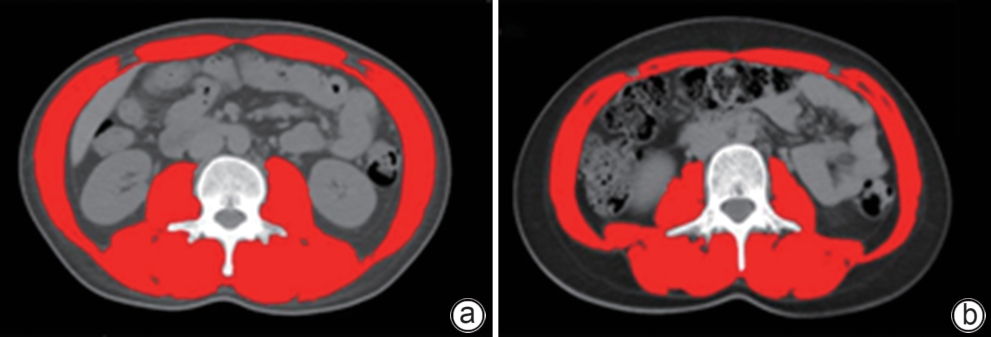

Objective To investigate the effect of dapagliflozin on liver lipid metabolism and gut microecology in mice with metabolic associated fatty liver disease (MAFLD), and to clarify its potential mechanism. Methods A total of 50 male C57 mice were randomly divided into Control group, type 2 diabetes+MAFLD group (MAFLD group), dapagliflozin group (DAPA group), meldonium group (THP group), and dapagliflozin+meldonium group (DAPA+THP group), with 10 mice in each group. High-fat diet combined with streptozotocin was used to establish a mouse model of MAFLD. Treatment outcomes were assessed based on histopathology and biochemical parameters such as blood glucose and blood lipid levels, and the transcriptomic and metagenomic analyses were used to identify differentially expressed genes and the changes in gut microbiota. A one-way analysis of variance was used for comparison of normally distributed continuous data between multiple groups, and the least significant difference t-test was used for comparison between two groups; the Kruskal-Wallis H test was used for comparison of non-normally distributed continuous data between multiple groups, and the Nemenyi test was used for comparison between two groups. Results Histopathological examination showed that the mice in the MAFLD group had excessive lipid deposition and hepatocyte steatosis; compared with the MAFLD group, the DAPA group had a significant improvement in hepatocyte steatosis, while the THP group and the DAPA+THP group had a less significant improvement compared with the DAPA group. Compared with the Control group, the MAFLD group had a significant increase in fasting blood glucose (P<0.05), significant increases in the serum levels of alanine aminotransferase (ALT), aspartate aminotransferase (AST), malondialdehyde, total cholesterol, triglyceride, and low-density lipoprotein cholesterol (P<0.05), and a significant reduction in high-density lipoprotein cholesterol (P<0.05). Compared with the MAFLD group, the DAPA group, the THP group, and the DAPA+THP group had significant reductions in the serum levels of ALT and AST (P<0.05). The results of 16S rRNA sequencing showed that compared with the Control group, the MAFLD group had significant changes in gut microbiota, with an increase in Firmicutes and a reduction in Bacteroidetes, as well as reductions in S24-7 and Erysipelotrichaceae and an increase in Lactobacillaceae. The levels of the above flora were upregulated to normal levels in the DAPA group, the THP group, and the DAPA+THP group. The liver transcriptomic analysis showed that the enriched metabolic pathways included steroid hormone biosynthesis, bile secretion, inflammatory mediator regulation of TRP, fatty acid elongation, and lipid biodegradation processes, and the related genes mainly involved the key targets of lipid metabolism such as Acot2, Angptl4, Scd2, and Npc1l1. Conclusion Dapagliflozin can alleviate MAFLD through the pathways such as steroid hormone biosynthesis, bile secretion, inflammatory mediator regulation of TRP, and fatty acid elongation, as well as by regulating gut microbiota homeostasis.